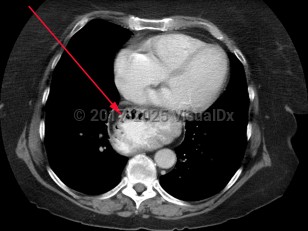

- Types II, III, IV: paraesophageal hernia – Herniation includes viscera other than the gastric cardia, including gastric fundus and the colon. In type II and III hernias, the stomach becomes "inverted," possibly leading to gastric volvulus.